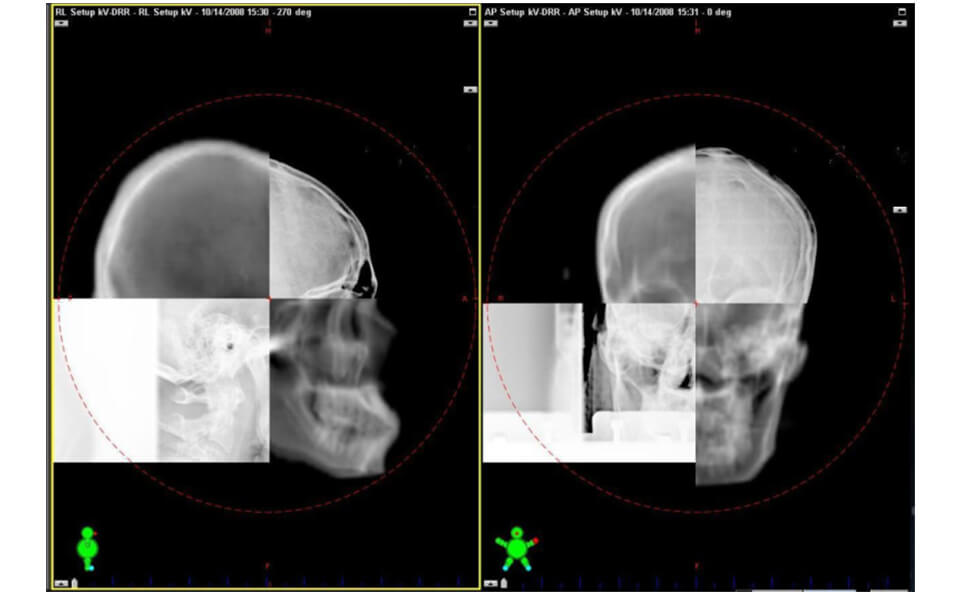

IGRT(画像誘導放射線治療)

治療装置に搭載されているOBI(ON BOAR IMAGE)でkV−X線画像を撮影し、その画像と治療計画CT画像から再構成された画像と位置合わせをします。また、CBCT(コーンビームCT)撮影を⾏い、照射位置微調整し位置精度を向上させます。これにより、正常な組織に放射線が当たることを最⼩限にします。

-

kV-X線画像と計画CT再構成画像との位置合わせCBCT

kV-X線画像と計画CT再構成画像との位置合わせCBCT